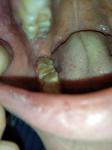

Здравствуйте, Никита Игоревич! Подскажите, пожалуйста, белые бугорки на слизистой вверху, около восьмерок - это гранулы Фордайса? Вычитала в интернете, что они являются вариантом нормы и лечения не требуют. Подскажите, правильно ли я все поняла? Спасибо!